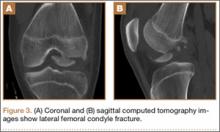

After reduction, an immediate return of normal patellar contour and patellofemoral tracking was observed as the knee was gently extended. There was no obvious defect to the patellar or quadriceps tendons, and the patient was able to perform a straight-leg raise, confirming the integrity of the extensor mechanism. Radiographs performed after the reduction confirmed relocation of the patella in correct anatomic position, as well as a lateral femoral condyle fracture (Figures 2A, 2B). Magnetic resonance imaging (MRI) of the knee confirmed no full-thickness quadriceps or patellar tendon tear. A computed tomography (CT) scan of the knee showed a comminuted fracture of the lateral femoral condyle in the coronal plane, as well as multiple bone fragments within the joint (Figures 3A, 3B). The patient was placed in a bulky soft dressing and underwent open reduction and internal fixation of the fracture.